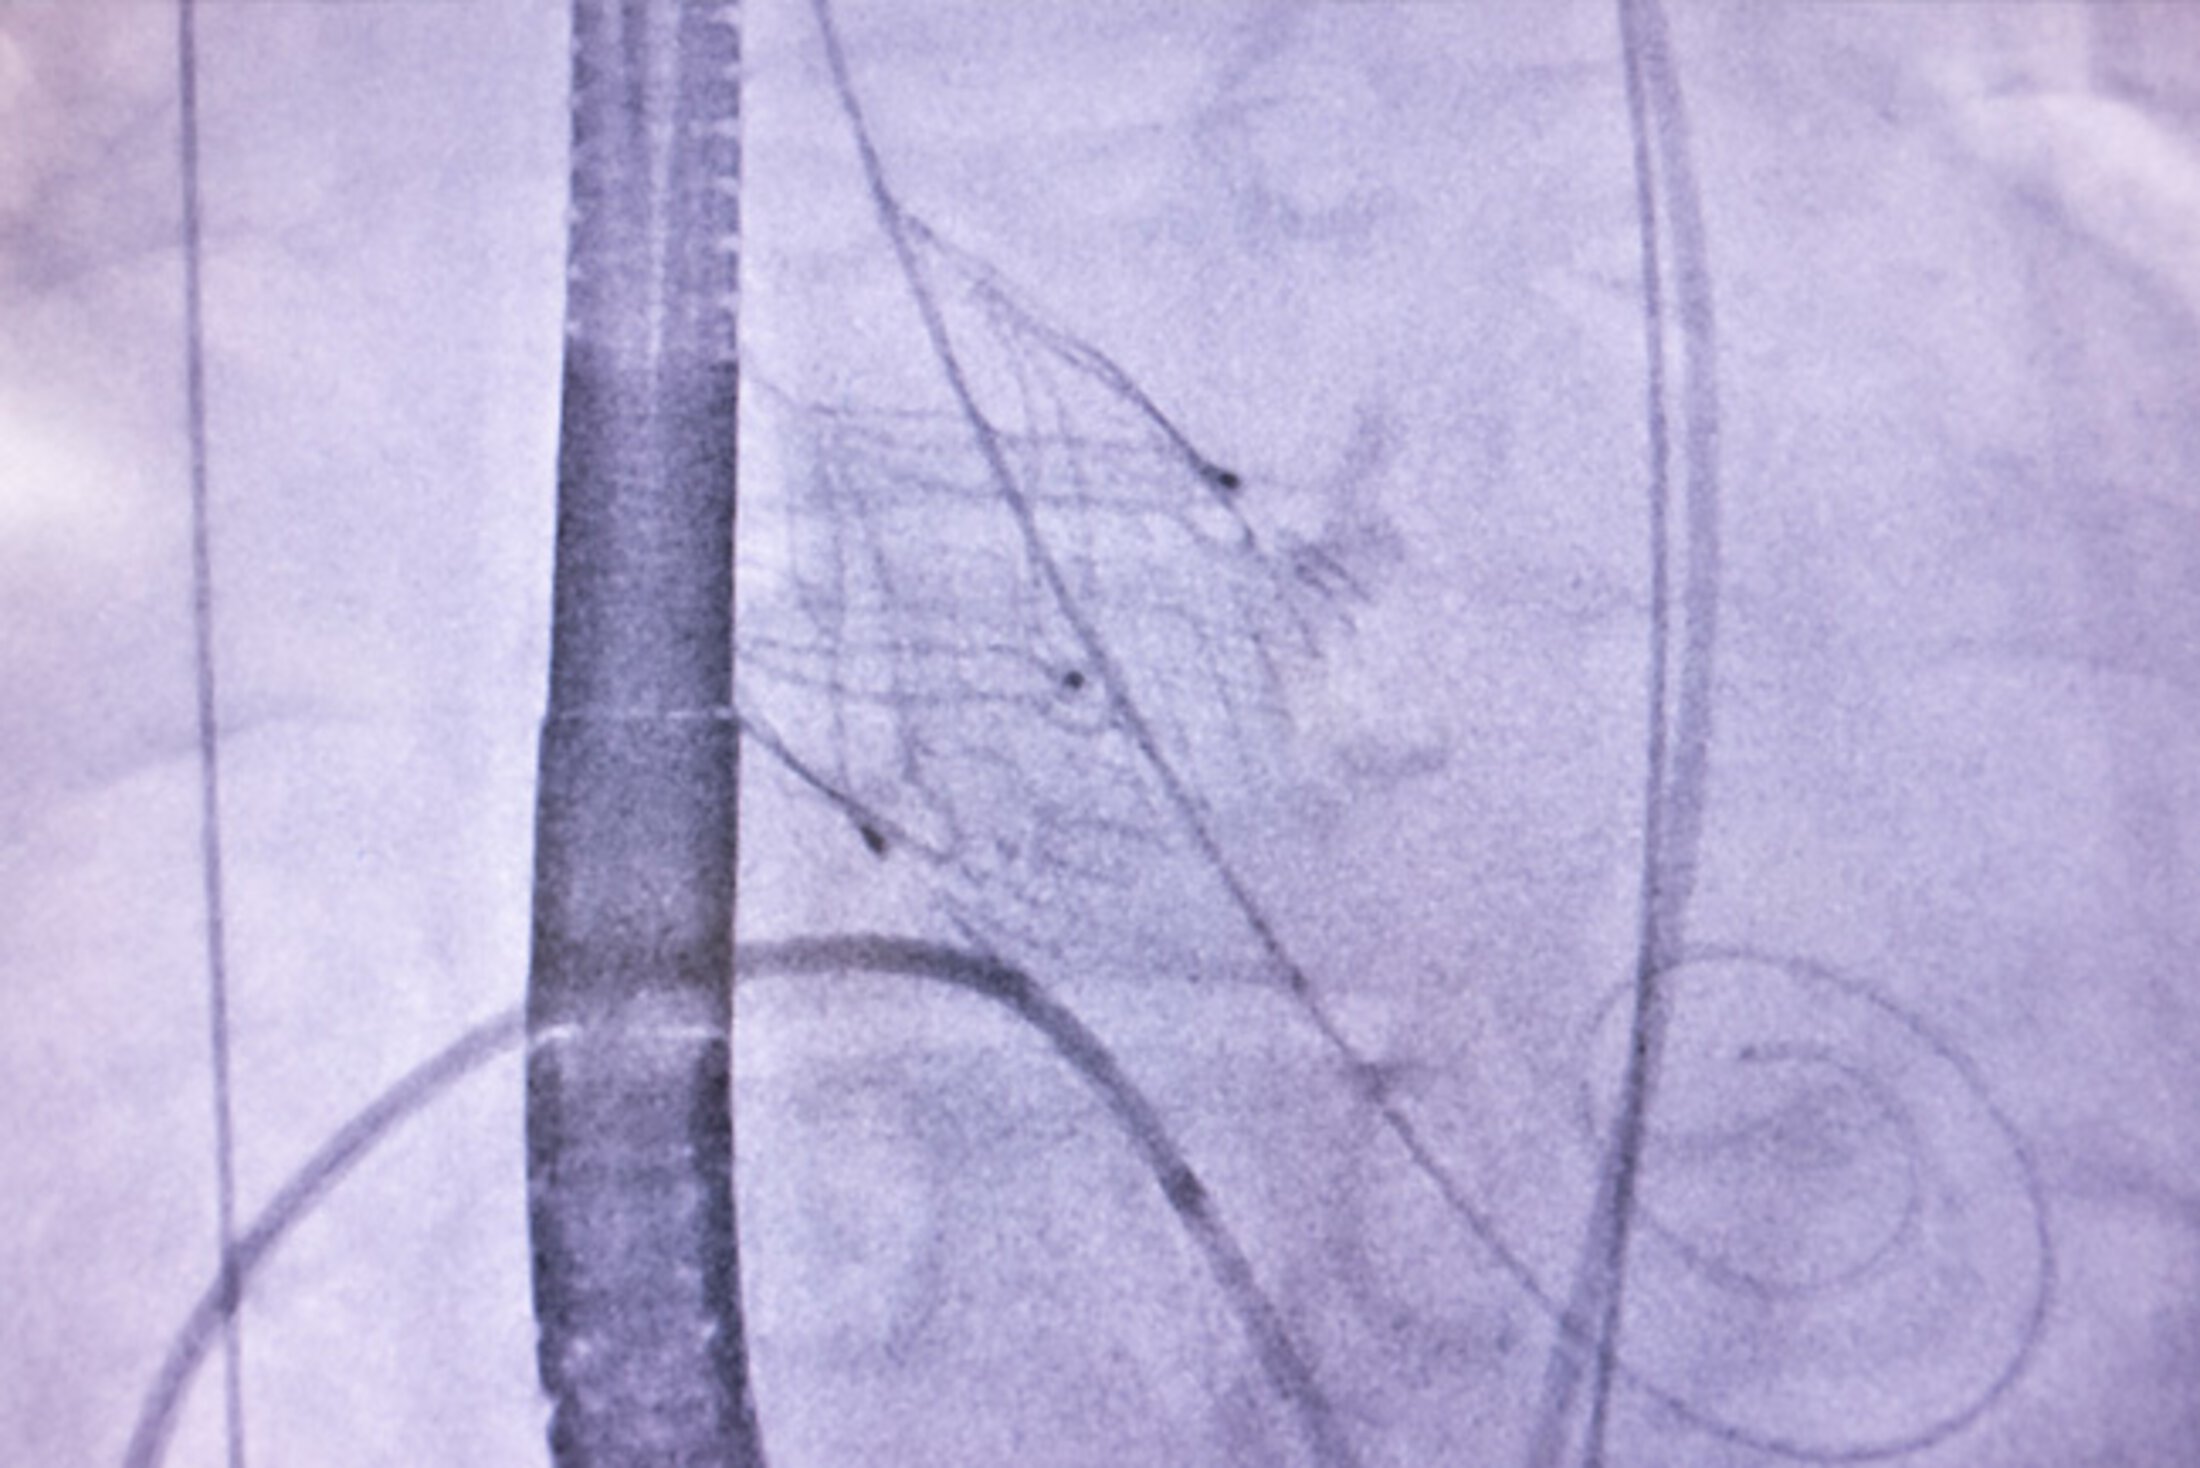

Amoroso and Ziegler gain access to the heart via a needle hole in the femoral artery in the groin. A long sheath is inserted until it reaches the aorta, which allows for the JenaValve to be safely deployed using a specialized clipping mechanism. The surgical field is visualized using ultrasound guidance as well as an x-ray camera. Once the grasp on the leaflets is confirmed, the team also confirms the leak is sealed by both fluoroscopy and transesophageal echocardiogram before releasing the valve and removing the delivery equipment.